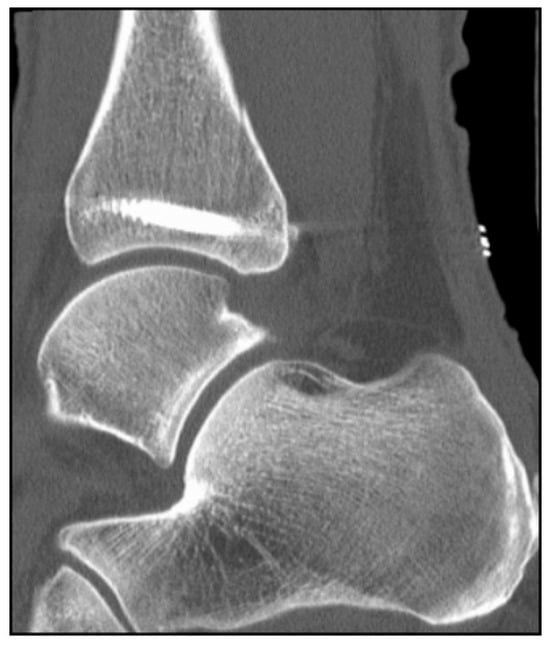

2. Preoperative Diagnostics

4. Classification

5. Case Description